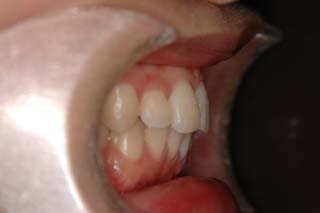

(上下顎前突/上下顎小臼歯抜歯)

装置撤去です。動的処置は2年弱でしたので、歯の移動させた距離で考慮すると、比較的短い治療期間でした。極めてよい咬合状態が得られたと思います。いずれも強い固定源を利用した結果の成果と考えられます。まだ、オーソアンカー SMAPシステム がそのまま残っているのが見えますが、もう必要ないので撤去して貰う予定です。今後は保定治療に移行し、数年にわたって咬合の安定状態を管理していきます。